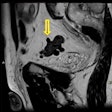

AI can detect cirrhosis accurately on MRI